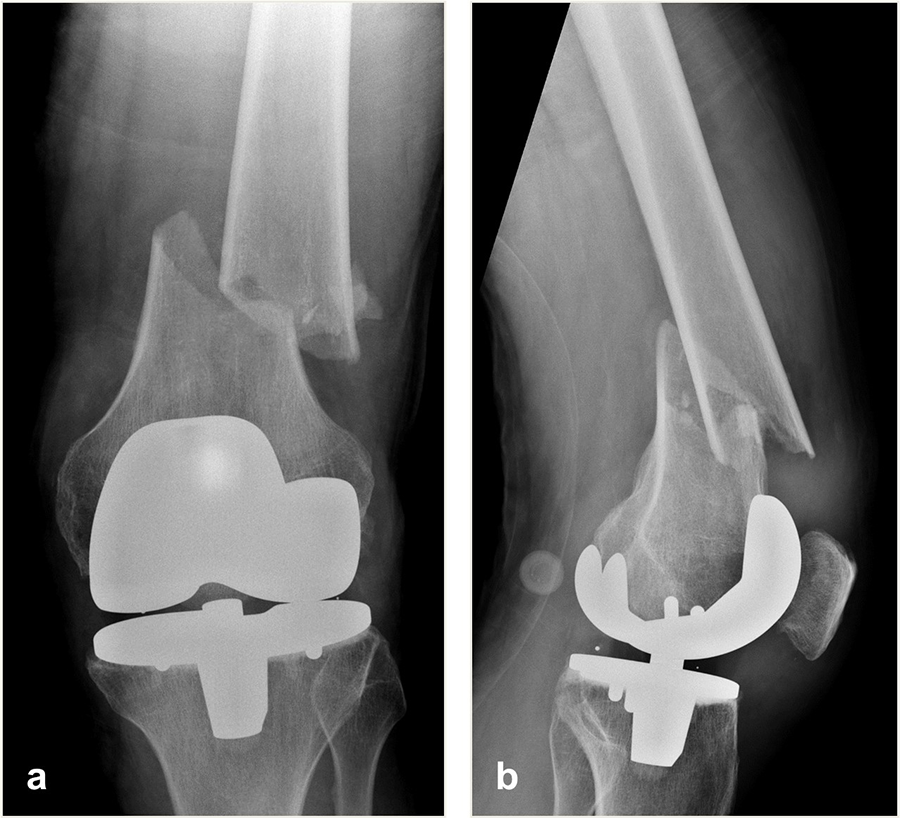

An 82-year-old man fell while climbing and sustained a periprosthetic distal femoral fracture (Fig 8). The fracture was reduced and then fixed with a Biphasic Plate DF (Fig 9). The patient was allowed immediate full weight bearing and presented with a decent amount of callus at the fracture site after 6 weeks (Fig 10).

The patient showed uneventful healing and returned to preoperative function 2.5 months postoperation. Figure 11 shows the callus formation 3 months postoperation.